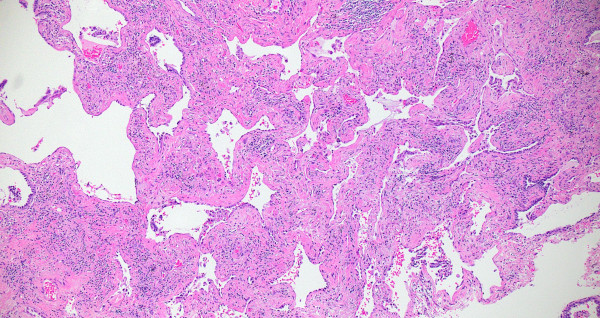

Compute tomography (CT) scan of the chest showed subpleural and peribronchial fibrosis with air-trapping on expiratory phase. The findings were read as likely “non-IPF pattern.” A serum antibody panel for hypersensitivity pneumonitis was positive for antibodies to Aspergillus flavus. Histologic sections of her lung biopsy demonstrated airways with peribronchiolar fibrosis with extensive metaplastic changes (Figure 1). Intra-alveolar giant cells and histiocytes with cholesterol clefts were seen (Figures 2-3). There were areas of interstitial inflammation and fibrosis resembling a cellular non-specific interstitial pneumonia (NSIP) pattern of injury (Figure 4). Also seen were extensive peribronchiolar metaplasia, microscopic “honeycombing”, interstitial giant cells, and poorly-formed granulomata (Figures 5-7).